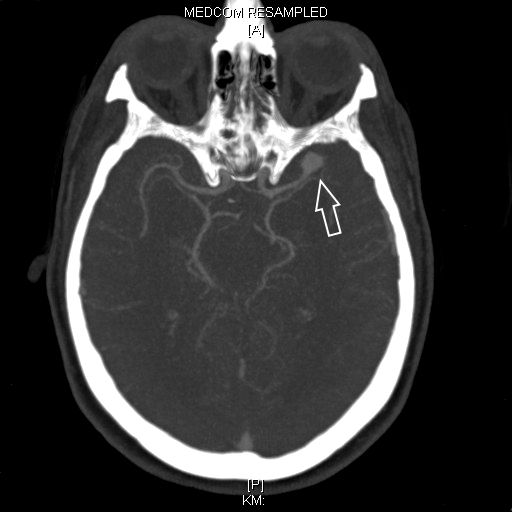

Als schnellste und sicherste Maßnahme gilt das craniale Computertomogramm (CCT). Hier lässt sich eine frische SAB meist zuverlässig darstellen, wobei auch bereits richtungsweisende Befunde, wie das Ausmaß der Blutung und eine eventuelle Lokalisation eines möglichen Aneurysmas bestimmt werden können. Darüber hinaus kann ein Angio-CCT, bei dem zusätzlich Kontrastmittel verabreicht wird und dann die intrazerebralen Blutgefäße gesondert rekonstruiert und dargestellt werden, weitere Informationen liefern. Der sogenannte “Goldstandard” zur Diagnose zerebraler Gefäßmissbildungen ist jedoch die zerebrale Angiographie. Dabei wird mit Hilfe eines speziellen Katheters über die Leisten- oder Armarterie Kontrastmittel gegeben und die zerebralen Blutgefäße hoch selektiv dargestellt. Sollten sich auf dem initialen CCT Zeichen des Hirnwasseraufstaus zeigen, der durch ein Verstopfen der Abflusskanäle durch das neu aufgetretene Blut bedingt ist, ist oft die Anlage einer Hirnwasserableitung nach außen notwendig (externe Ventrikeldrainage).

CT Bildgebung der klassischen subarachnoidalen Blutverteilung nach SAB